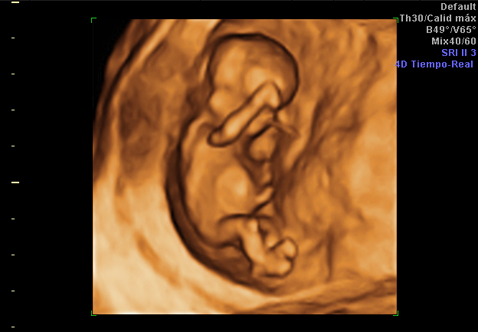

• Ecografía 4d del primer trimestre

¿Qué es una ecografía en 4D? Ventajas de realizar la ecografía en cuatro dimensiones y en qué semana del embarazo se recomienda

Inés Tamarit Dagenhardt

Inés Tamarit Degenhardt ‑ ginecología y obstetricia